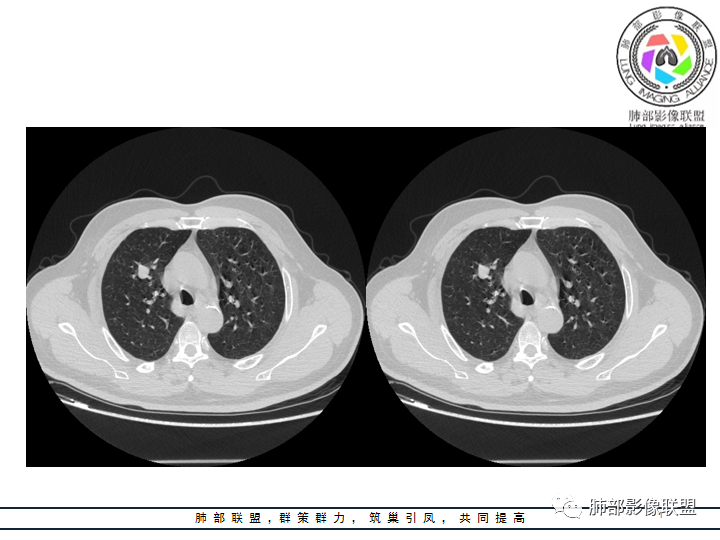

影像资料

老年男性患者,长期吸烟史,没有呼吸系统临床表现。胸部CT示右肺上叶实性密度结节影,密度均匀,未见空洞及钙化,边缘较光整,未见分叶及毛刺。血管影旁现侧出,支气管进入并截断,不均匀强化。

影像上结节影或块影一旦与支气管密切相关(如截断),不支持硬化性肺细胞瘤、错构瘤、孤立性纤维瘤等良性病灶。如此清晰的边缘也不符合一般意义上的炎性渗出。